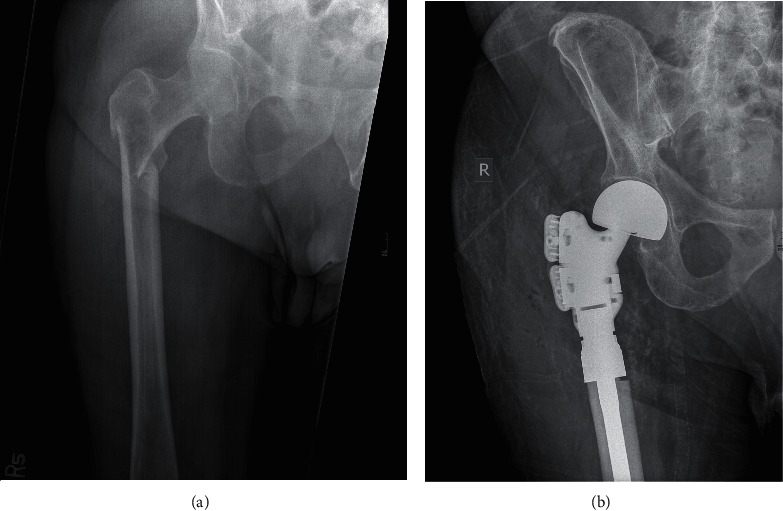

本研究的目的是评估复查童子军CT图像的好处,获得常规肿瘤监测,早期识别病理性骨病变。回顾性分析了2009-2019年在某三级医疗机构接受两名骨科肿瘤外科医生手术治疗的病理性病变或肱骨或股骨骨折患者。我们回顾了影像学记录,以确定该队列中在正式诊断骨病变或骨折之前有CT扫描视图的患者。CT扫描图像由两名独立审查员评估,以确定任何病理病变,并审查x线片报告,以确定在初始扫描解释时放射学是否注意到病变。144例患者被确定,其中39例在正式诊断病变之前有可用的侦察CT图像。25例(64.1%)患者在侦察CT上发现病变,而只有9例(23.1%)患者的病变在最初的CT放射学报告中被记录。研究作者在侦察CT上共发现了29个病变,其中19个(65.5%)在最初的放射学解释中未报告,作者观察到的平均间隔时间为202天正式诊断。在即将发生的骨折中,3名患者(16.7%)在转诊到骨科之前发生了完全骨折,这些在侦察CT上未发现的病变与表现为骨折的平均间隔时间为68天。本研究提倡仔细审查所有的童子军CT成像作为转移性疾病工作的重要组成部分,并鼓励所有从业人员利用这种筛查工具来识别病理性骨病变,这可能有助于加快早期治疗以减少患者的发病率。

The purpose of this study is to evaluate the benefit of reviewing scout CT images, obtained for routine oncologic surveillance, for the early identification of pathologic bony lesions. A retrospective review was conducted on patients who previously underwent surgical treatment by two orthopedic oncology surgeons at a tertiary care institution from 2009-2019 for pathologic lesions or fractures of the humerus or femur. Radiographic records were reviewed to identify patients in this cohort who had available scout views from CT imaging prior to official diagnosis of the bony lesion or fracture. CT scout images were assessed by two independent reviewers to identify any pathologic lesions, and radiographic reports were reviewed to identify if the lesions were noted by radiology at the time of the initial scan interpretation. One hundred and forty-four patients were identified, and thirty-nine had an available scout CT image prior to official diagnosis of the lesion. Twenty-five patients (64.1%) had lesions identified by authors on scout CT versus only 9 (23.1%) who had lesions that were documented in the initial CT radiologic report. There was a total of 29 lesions identified by the study authors on scout CT, and 19 (65.5%) were not reported in the initial radiographic interpretation with an average interval between observation by authors and official diagnosis of 202 days. Of the impending fractures, three patients (16.7%) went on to complete fracture prior to referral to orthopedics with an average interval between these missed lesions on scout CT and their presentation with fracture of 68 days. This study advocates for the careful review of all scout CT imaging as an essential part of the work up for metastatic disease and encourages all practitioners to utilize this screening tool for the identification of pathologic bony lesions which may help expedite early treatment to reduce patient morbidity.